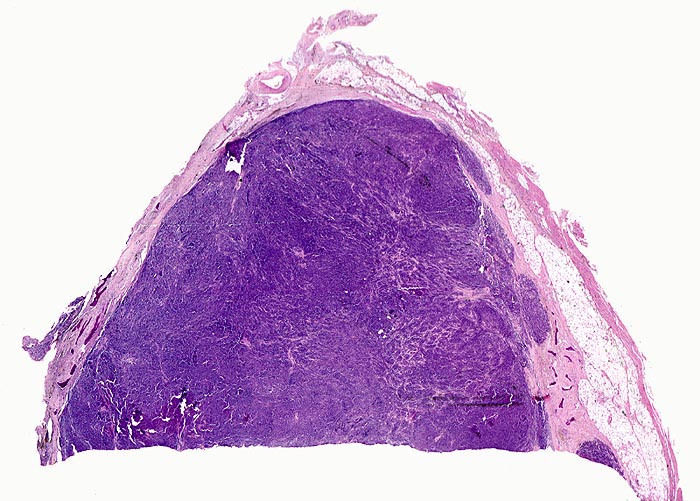

PathoPic – image database / PathoPic ID 4141 - Plasmazellmyelom

Plasmazellmyelom

Knochenmark, Wirbelkörper

Von schmalen bindegewebigen Septen durchzogene solide basophile Tumormasse ohne erkennbare Markstrukturen. Im Randbereich sind einzelne Knochenbälkchen erkennbar.

Notfalleinweisung wegen umschriebenen Thoraxschmerzen ohne adäquates Trauma. Im Röntgenbild Nachweis multipler Frakturen der Wirbelsäule und der Rippen bei grobsträhniger Osteoporose. In der Serumelektrophorese Nachweis einer Paraproteinämie.

Diagnosesicherung: Immunhistologischer Nachweis von monoklonalem Immunglobulin (IgG oder IgA und kappa- oder lambda-Leichtketten in einem Verhältnis von >1:16 bzw. >16:1). Klinisch entsprechender Nachweis einer Paraproteinämie oder Proteinurie (Bence-Jones Protein = monoklonale freie Leichtketten).